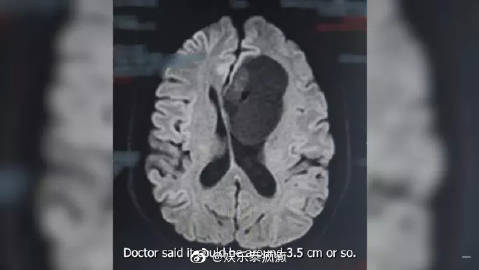

Pok透露自己近段时间有莫名的头疼,经过多方会诊后都查不出原因,最后进行磁力共振时才发现一颗乒乓球大的肿瘤,于是他第一时间接受了手术切除,而后发现肿瘤比预期的大,竟已是网球般的尺寸,但幸好切片后发现肿瘤并非恶性,能够痊愈,就连医生都觉得他很幸运。